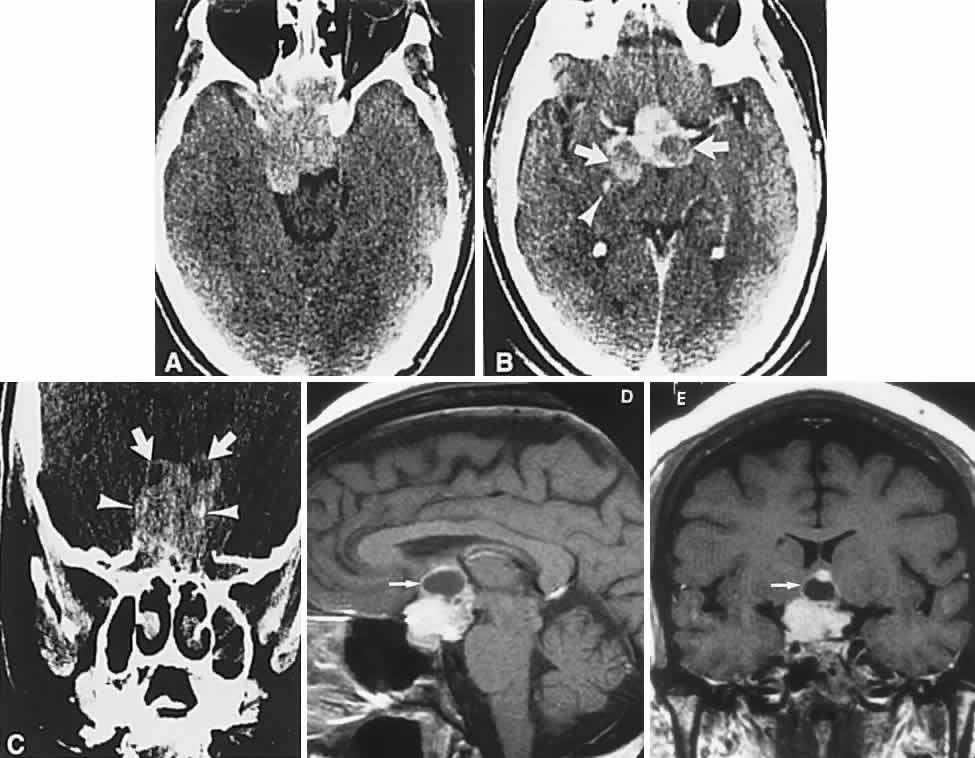

Clinical signs and symptoms include the following: acute onset of severe headache, often sickening frontal or retro-bulbar cephalgia, or other less disabling change in headache pattern; acute or rapidly progressing unilateral or bilateral (usually asymmetric) ophthalmoplegia due to rapid expansion into cavernous sinuses (see also Volume 2, Chapter 12); epistaxis or CSF rhinorrhea when the mass ruptures or erodes into the sphenoid sinus; complications of blood or necrosis debris in the CSF, with “pseudomeningitis”; rapid neurologic deterioration and obtundation, although patients need not be stuporous; and, greater or lesser degrees of hypopituitarism.62,63 Selective expansion laterally into the cavernous sinus may produce ophthalmoplegia without visual loss; selective expansion superiorly may produce visual loss without ophthalmoplegia. Almost without exception, enlargement of the sella is found even on plain skull film views; both CT and MRI detect fresh hemorrhage (Fig. 3), but MRI may fail to demonstrate acute hemorrhage unless specific sequences are employed (hemorrhage may be isointense on T1-weighted images and hypointense on T2-weighted images; in the subacute phase, extracellular methemoglobin should appear bright on both T1 and T2 sequences). Corticosteroid replacement and other supportive measures may be critical, and, in most instances, decompression through the sphenoid sinus is advisable, sooner rather than later. Bromocriptine has been suggested as a temporizing measure when signs and symptoms are modest and not progressing,64 and there are advocates65 for conservative management consisting of intravenous dexamethasone, so long as visual deficits are minimal or rapidly improve; otherwise decompressive surgery is required. Given the regularity with which pituitary apoplexy is often a delayed diagnosis, being confused with ruptured aneurysm or meningitis, for example, and that transsphenoidal surgery is a relatively simple undertaking, further procrastination in decompression of the compromised visual pathways is to be avoided.

Fig. 3. Neuroimaging of pituitary adenomas. A. Axial computed tomography (CT) section shows a round tumor mass filling the suprasellar cistern; ring enhancement (arrows) indicates subcapsular hemorrhage. B. Contrast-enhanced coronal CT section through a large invasive adenoma. Note encasement of the carotid artery (arrows) and the position of the middle cerebral artery above (arrowheads). C. Axial CT section shows lateral expansion into the cavernous sinuses (white arrows) and a necrotic cyst (black arrow). D. Subfrontal superior extent of the mass. Note the middle cerebral arteries. E. Magnetic resonance imaging of a large lobulated prolactinoma, with suprasellar extension. Note the distortion of the third ventricle (open arrows) and extension toward the temporal lobe (long arrow); the tumor has not involved the sphenoidal sinus (s). F. Chiasm (arrowheads) is draped on the superior surface of the tumor (TR, 550 milliseconds; TE, 26 milliseconds). G. Sagittal section shows suprasellar growth with the chiasm above (arrowheads); the sella (arrows) and sphenoidal sinus (s) are normal (TR, 850 milliseconds; TE, 26 milliseconds). H. Hyperintense signal (TR, 2000 milliseconds; TE, 60 milliseconds) indicates the partial cystic character. Sagittal (I) and axial (J) sections with head tilt to the right, in case of a large cystic adenoma with an interface level between newer blood (white arrow) and older blood (black arrow) (TR, 800 milliseconds; TE, 30 milliseconds). K. Signal difference is intensified (TR, 2100 milliseconds; TE, 80 milliseconds). L. Hemorrhage (bright signal, arrow) in a pituitary adenoma with headache and bitemporal field depressions. M. Without interventions, 2-month follow-up showed spontaneous involution, with normal pituitary gland (arrow), stalk, and chiasm.

Imaging of Pituitary Tumors

In addition to the radiologic implications mentioned previously, specific points should be emphasized. Contrast-enhanced CT and, especially, MRI have replaced all previous radiologic techniques in the detection and anatomic assessment of sellar and juxtasellar lesions. MRI has also the inherent advantage of using no radiation, nor does it require iodinated contrast injections. Although thin-section contrasted CT does indeed disclose most lesions, bone changes, and recent hemorrhage, MRI is superior in delineating distortions of optic nerves and chiasm, in displaying arteries, and in revealing fat, hemorrhage, or cyst (see Figs. 3E through M). Indeed, in a prospective study of normal volunteers, gadolinium-enhanced MRI disclosed pituitary adenomas (3 mm to 6 mm in diameter, i.e., microadenomas) in 10% of adults aged 18 to 60 years.66 T2-weighted fast spin-echo MRIs are currently the most precise sequence for demonstrating the optic nerves and chiasm, even when these structures are severely distorted by suprasellar tumor extension.67